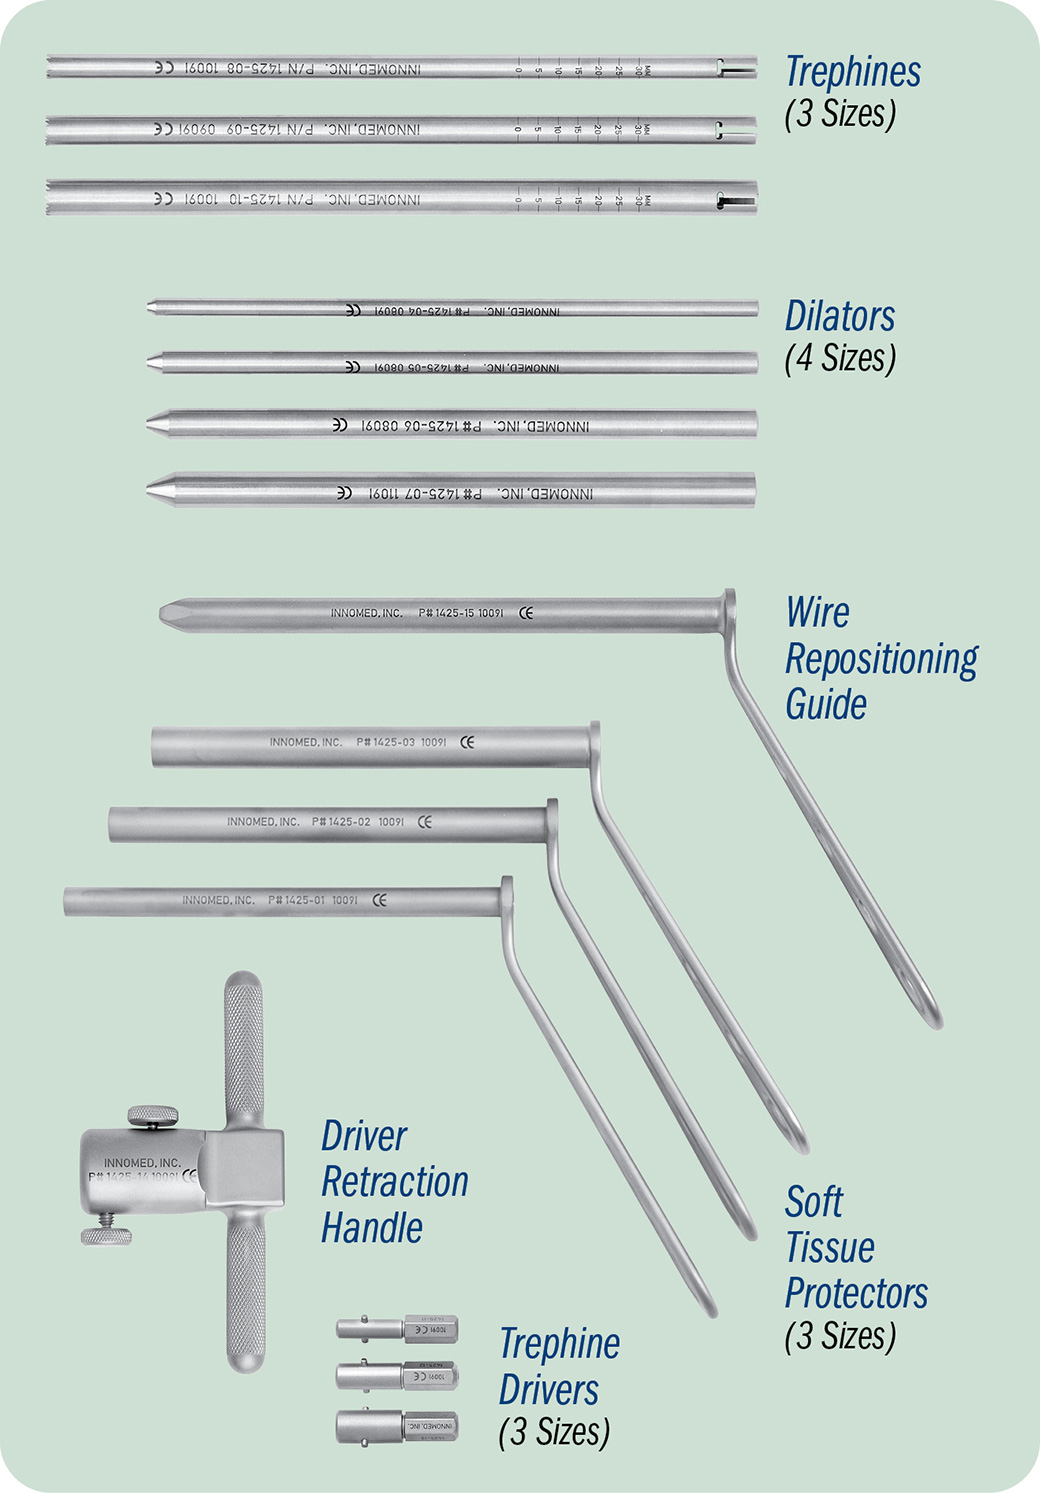

Set Includes/Available Separately:

1425-01 [Soft Tissue Protector – Small]

1425-02 [Soft Tissue Protector – Medium]

1425-03 [Soft Tissue Protector – Large]

1425-04 [Dilator – 4.75 mm]

1425-05 [Dilator – 6.25 mm]

1425-06 [Dilator – 7.75 mm]

1425-07 [Dilator – 9.25 mm]

1425-08 [Trephine – Small 5 mm]

1425-09 [Trephine – Medium 6,5 mm]

1425-10 [Trephine – Large 8 mm]

1425-11 [Drive End – Small]

1425-12 [Drive End – Medium]

1425-13 [Drive End – Large]

1425-14 [Driver Retraction Handle]

Includes (2) Handle Retaining Screws (#1425-14-B-COMP)

1425-15 [3-Hole Wire Repositioning Guide]

1425-Case [Case]